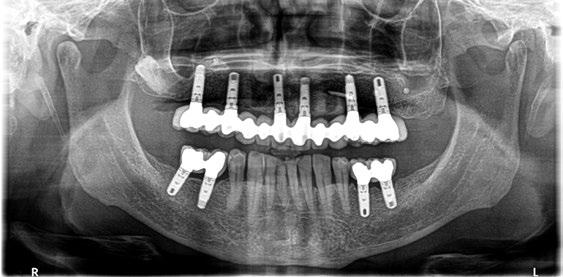

Figura 27. Ortopantomografía del provisional atornillado en boca para verificar ajuste.

ortopantomografía de verificación del ajuste pasivo de todos los implantes. Por último, tapamos las chimeneas con teflón y resina provisional y se chequeó nuevamente la oclusión, dando nuevamente las instrucciones de higiene y mantenimiento de la prótesis provisional (Figuras 24-27).